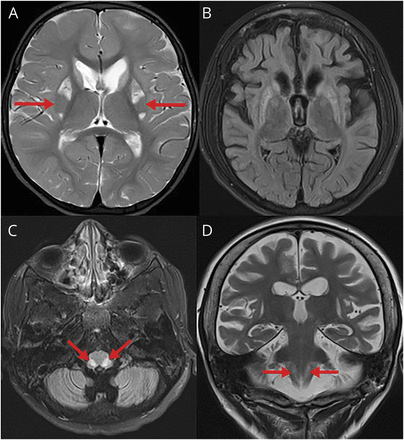

一个七岁的女孩MEGD (H) EL [3-methylglutaconic酸尿,dystonia-deafness,(肝病)、脑病,Leigh-like综合症,SERAC1]1面对日益恶化的呼吸妥协。评估显示II型呼吸衰竭(如hypercapnic)需要机械通气。脑MRI显示进展MEGD已知的变化(H)埃尔(图中,A和B)和对称核束solitarius (nt)参与(图中,C和D)。她呼吸机依赖,随后死于疾病的效果。

脑部核磁共振成像

2岁大脑核磁共振显示了典型的“putaminal眼”(A,箭头)。MRI在7岁显示进步的萎缩和胶质增生的基底神经节和大脑皮层萎缩(B)和双边对称信号变化的核束solitarius液体衰减反转恢复序列在t2加权像(C,箭头)和(D,箭头)。